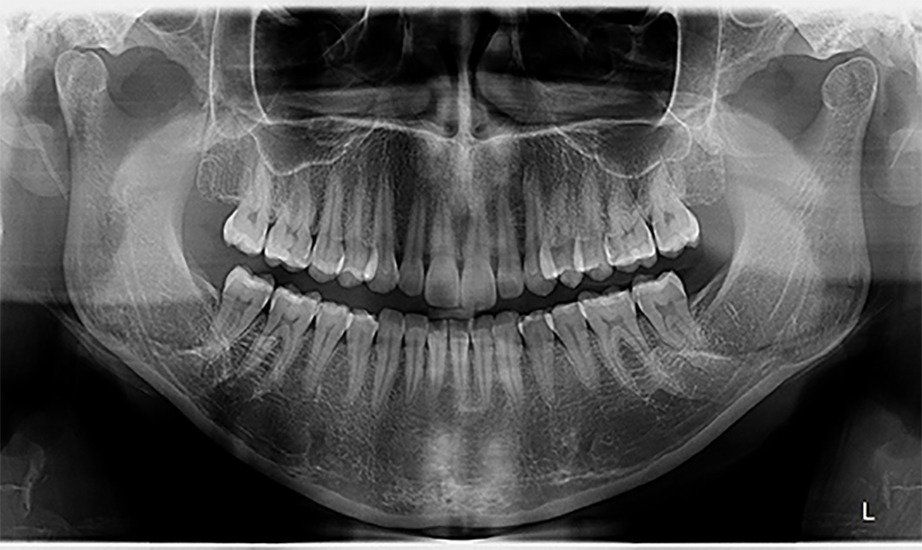

A radiologia odontológica digital oferece uma série de benefícios as pessoas e profissionais. Ela dispensa filmes radiográficos, oferece maior precisão em resultados, armazenamento de arquivos digitais com mais praticidade, que pode ser retirada através da internet ou por e-mail, menor exposição à radiação, e maior agilidade. Ao contrário da radiografia, que precisa ser revelada, a radiologia digital envia diretamente a imagem para o computador, deixando o processo de diagnóstico mais ágil, sem necessidade de esperar alguns dias para o exame ficar pronto.

Atende seus pacientes com a máxima precisão, cuidado e agilidade que o momento pede. A clínica está em constante atualização para trazer o que há de mais moderno em radiologia Odontologica digital. Atendemos por ordem de chegada, não necessitando agendamento prévio.